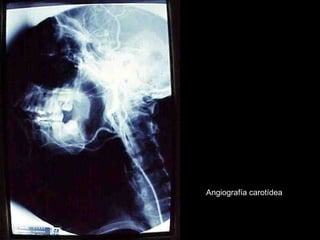

Angiografía carotídea